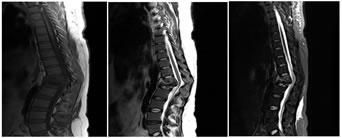

A: SAGITTAL T1W; B: SAGITTAL T2W C: SAGITTAL STIR;

D: AXIAL T1W; E: AXIAL T2W

Figure 1: 28 year male presenting with fever and mid backache. Kyphotic deformity due to collapse of T4 and T5 vertebral bodies with near complete obliteration of T4-T5 intervening disc space (A, B, C). Prevertebral and paravertebral abscess seen extending into epidural space. Significant cord compression noted (D, E)